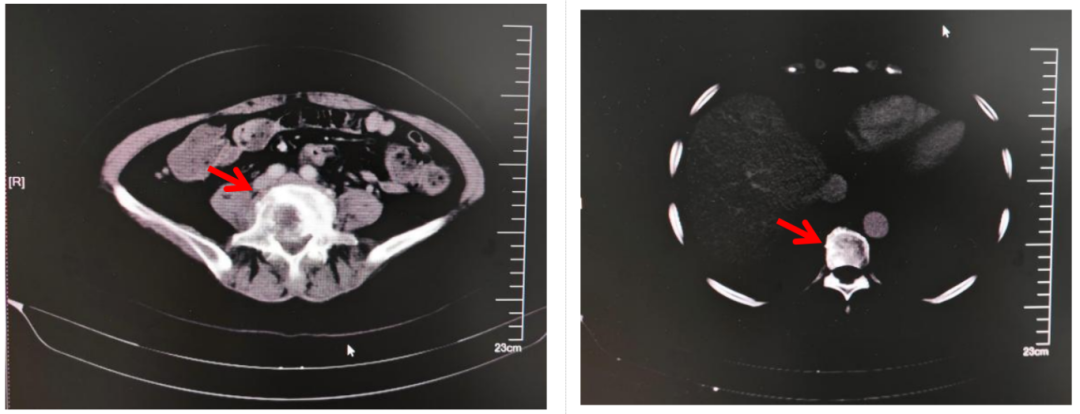

影像学检查:2025.02.05:胸腹部增强CT:右肺门-右肺上叶不规则软组织影,整体较前范围增大,积气较前减少;远端肺组织阻塞性肺炎、肺不张,较前范围稍增大。纵隔及右肺门多发淋巴结,部分较前增大。双肺散在小结节,部分较前增大。双肺少许炎性改变,较前相仿;双侧胸膜增厚,局部较前明显。甲状腺密度欠均,较前相仿。双肾低密度灶,右肾大者较前增大,转移?余较前相仿。T9及L5椎体骨质破坏,转移可能,较前相仿。(如下图所示)